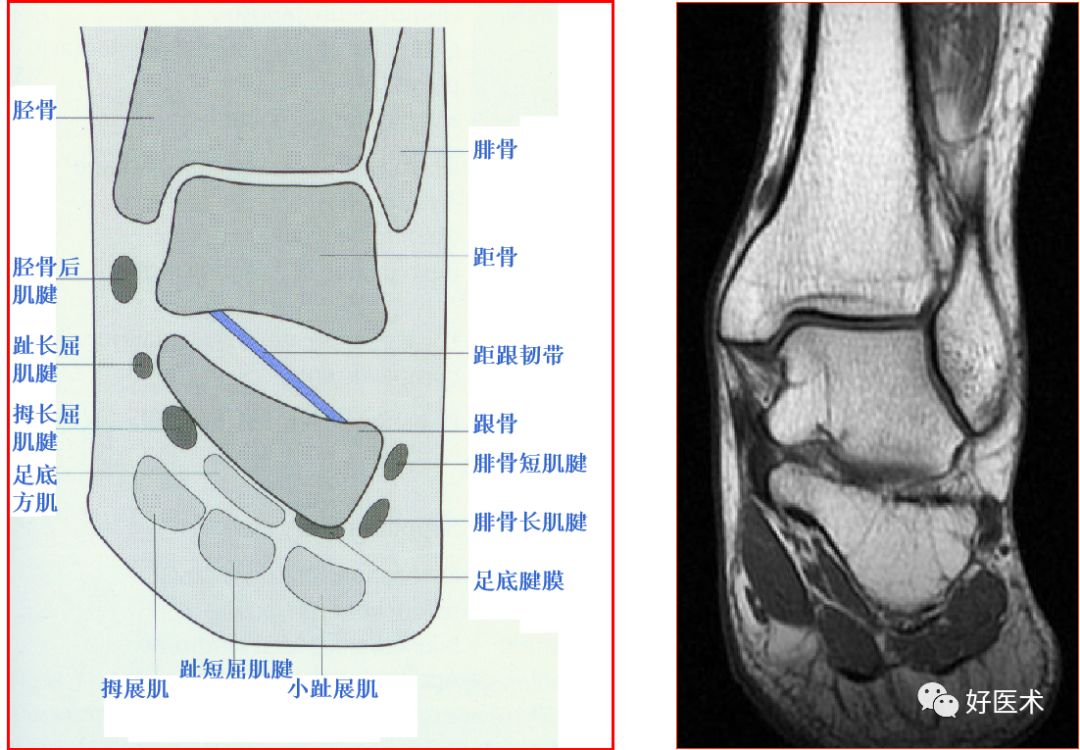

一、解剖和扫描方法

胫骨后肌肌腱撕裂

踝关节的韧带

距跟韧带

跟腓韧带